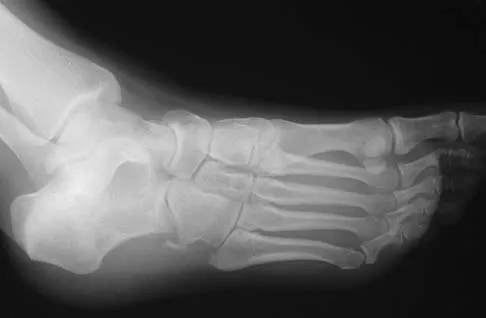

A 28-year-old man has had a 2-year history of progressive lateral ankle pain. History reveals that he underwent a triple arthrodesis at age 13 for a tarsal coalition. The pain has been refractory to braces, custom inserts, and nonsteroidal anti-inflammatory drugs. Weight-bearing radiographs of the ankle and foot are shown in Figures 3a through 3d. Surgical management should include which of the following?